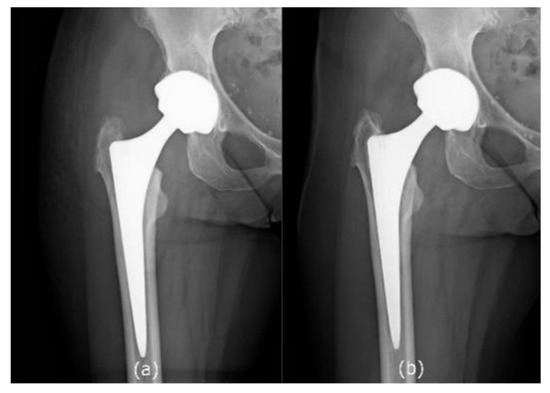

2.2. Radiological Outcomes